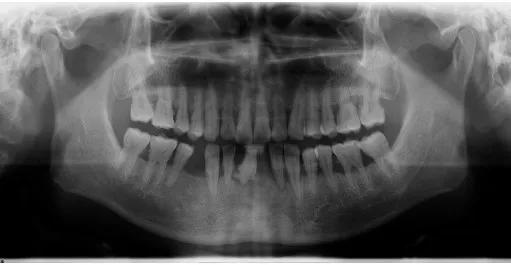

今年40出头的郑先生

是个老烟枪,且平时不注意口腔卫生

好多颗牙齿都松动了

吃东西都受影响

于是来苏州科技城医院口腔科就诊

医生检查发现,原来郑先生得了

慢性牙周炎

前牙多颗牙因牙周组织破坏严重

只能拔除

余留牙通过口腔卫生宣教

牙周基础治疗(洁牙,刮治等)

牙周手术治疗

及牙周维护治疗等牙周炎症控制稳定

预后较好